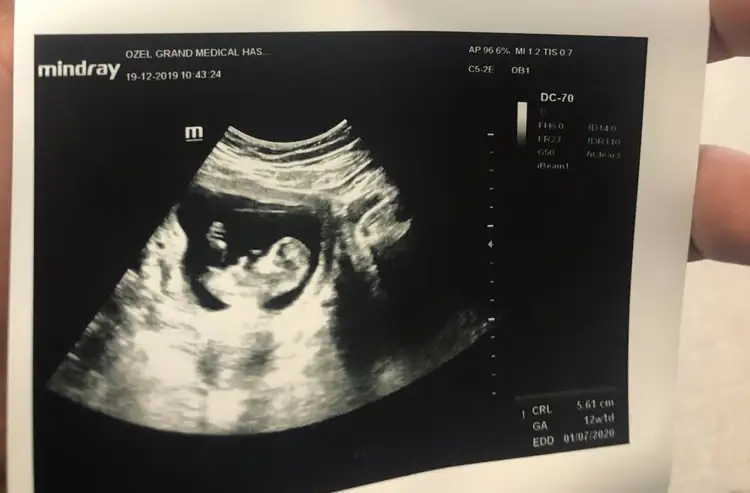

dün gittik 14 hafta usg verdi ama belli olmuyor

2. bebekİlk bebekmi saglıkla gelsin minnoş geri dönüş için mutlu olurum![]()

Maşallah2. bebek1 oğlum var 6 yaşında